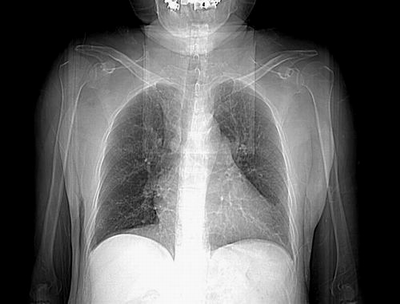

患者,男,60岁,病史如下:

2008.8.11胸片

病变从8.11-8.17明显改变,增多,以蜂窝状改变为主,类蜂窝肺,似弥漫性肺泡癌,但是病变进展太快,不符合弥漫性细支气管肺泡癌。因此考虑为特殊微生物感染,多以霉菌类常见,建议细菌微生物学检查。

结合临床慢支炎肺气肿,肺心病病史,三次胸片观察可见病情发展变化迅速,病情凶险,考虑多重感染伴ards.